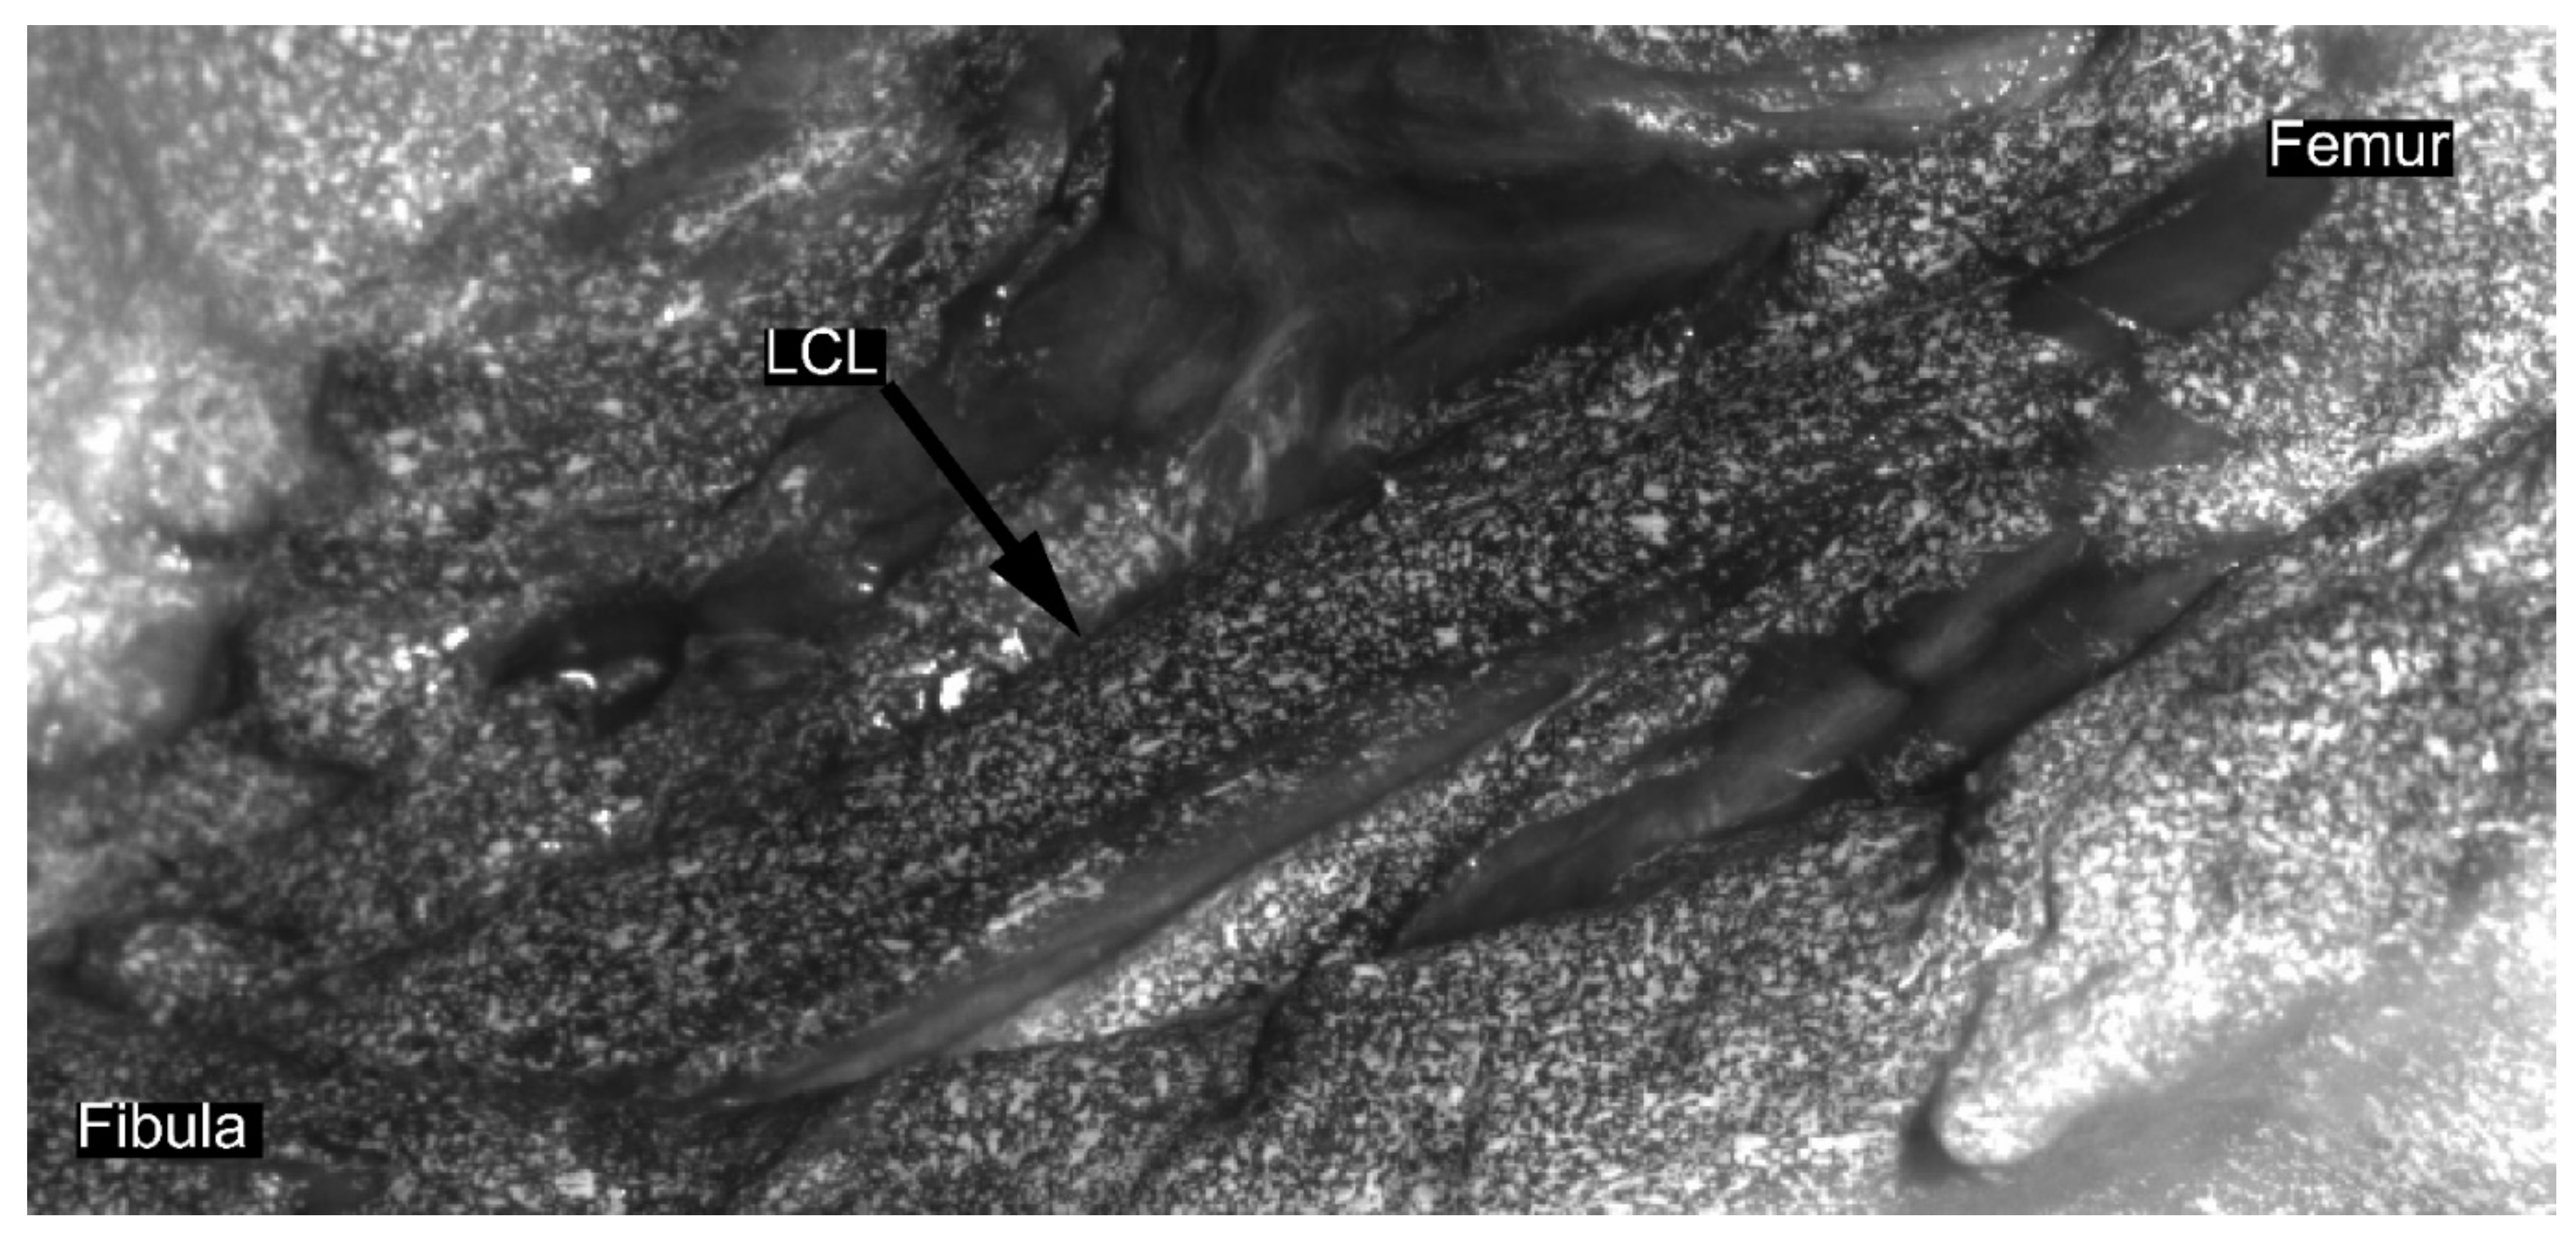

In a second series of loading cycles, DIC data were collected. For each DIC acquisition, three loading cycles were recorded in order to replicate the aforementioned cyclic loading conditions. Ligaments were prepared for DIC acquisition following similar methodology to the previous studies on soft tissues [6,14,16]. Diluted methylene blue was applied on the ligament to create background and contrast. Then, a speckle pattern was applied on the ligament with water-based white paint using an airbrush gun [17] (Figure 2). Afterwards, two high-resolution cameras (Flir Grasshoper3 GS3-U3-51S5M-C 5MP) with large field-of-view (FOV) lenses (Schneider Kreuznach Apo-Xenoplan 1.4/23) were placed, taking into account the optical properties of the lenses and the required FOV. Subsequently, the DIC system was calibrated for the acquisition using commercial software VIC3D (v8, Correlated Solutions, Inc., Columbia, SC, USA). Afterwards, data were recorded in triplicate at 20 Hz throughout the three loading cycles. Camera acquisitions were triggered and synchronized by the motion capture system’s trigger signal.

Figure 2.

Representative speckle pattern for lateral collateral ligament prior strain computation using digital image correlation. First, diluted methylene blue was applied on the ligament to create a dark background; then, a speckle tracking was applied with white paint using an airbrush gun, following the previously published procedure [17].